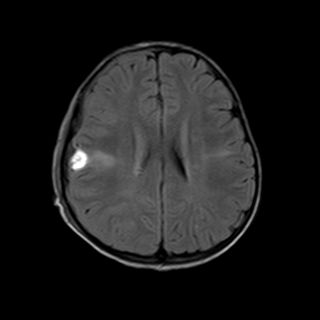

术后,小月恢复良好,没有出现癫痫发作。

术后MR